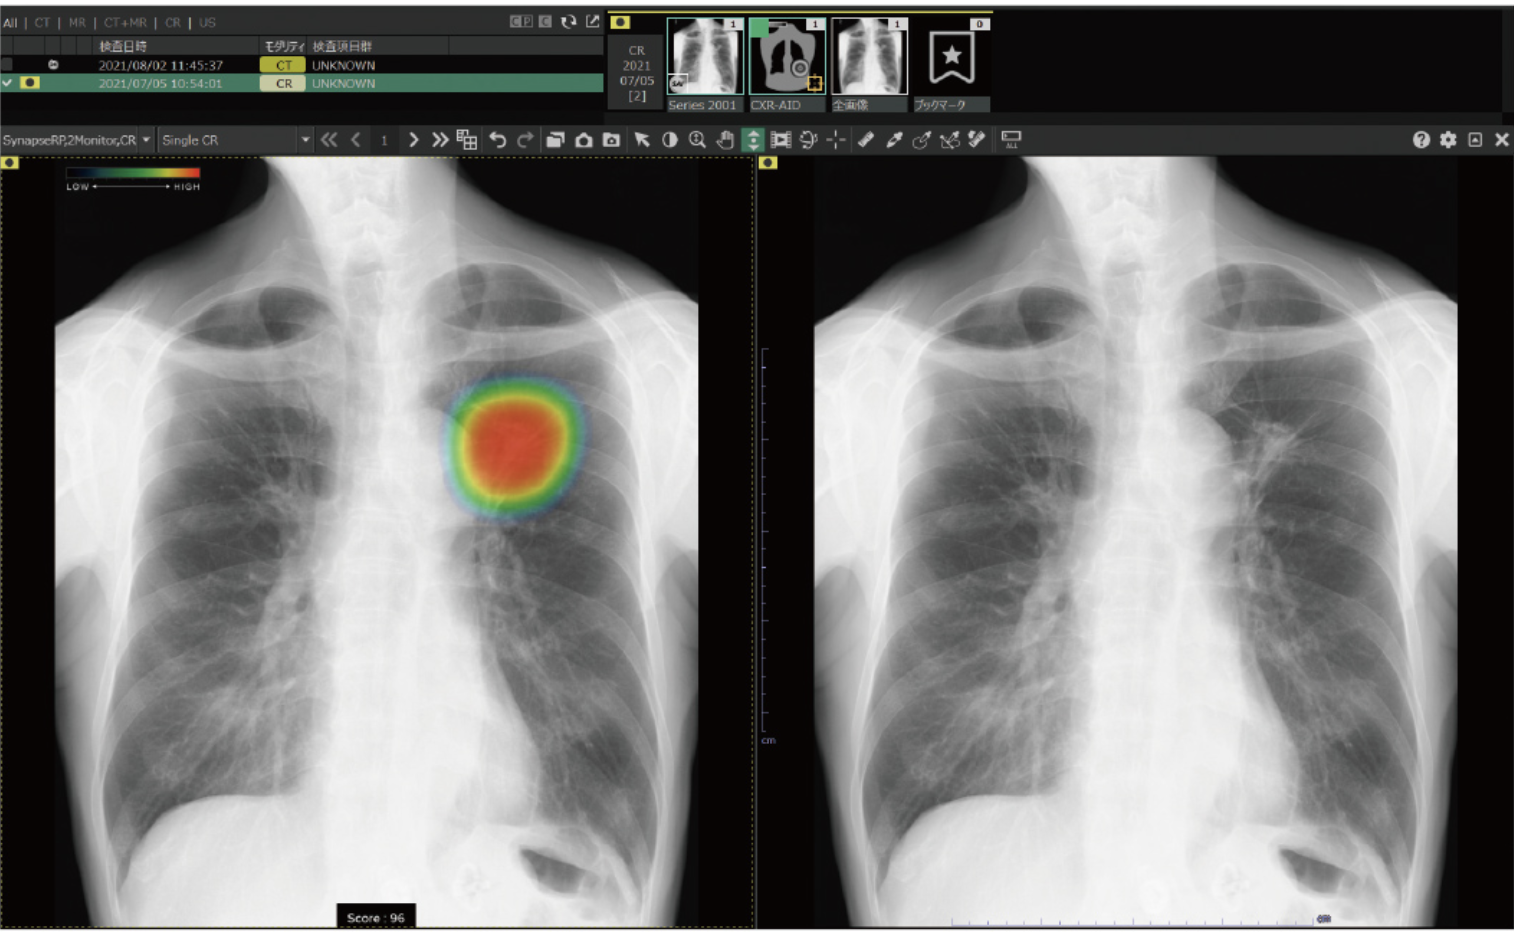

医療現場での画像診断

クラウドAIは、医療現場の画像診断でも活用されています。

クラウドAIによる医療現場の画像診断技術には、過去の症例データなどをAIに学習させて、画像から異常を検知するサービスなどがあります。例えば、富士フイルムが提供する医療クラウドサービスは、X線/CT/MRIなどの画像から異常を検知するサービスです。

このクラウドAIを活用した画像診断技術の登場によって、より効率的な診断が可能となり、医療サービスの向上につながっています。